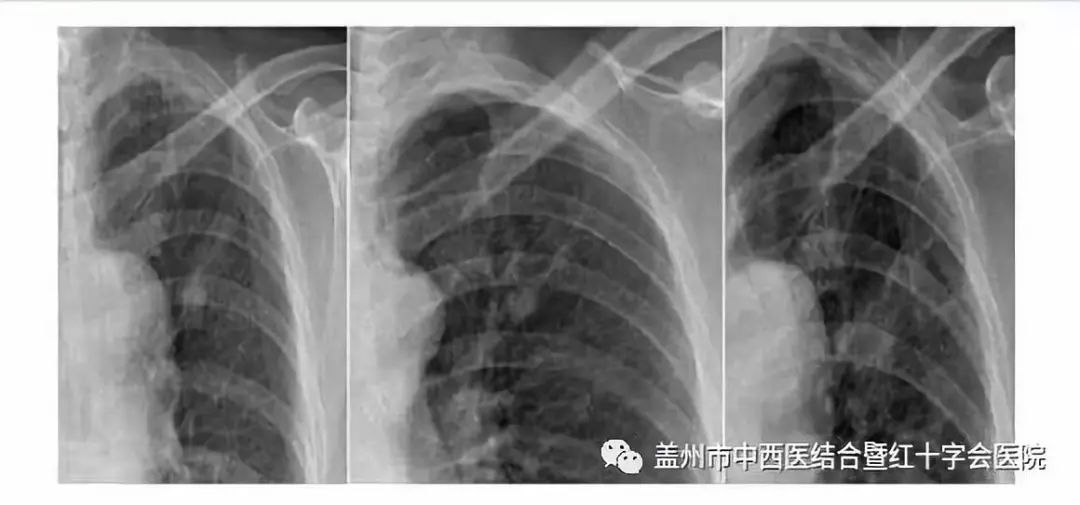

案例:患者 66岁 数月前在家感到身体不适,伴有咳嗽现象,身体消瘦。

于今年2月前往某医院就诊,到院后该院为患者进行CT检查后,初步诊断为肺部炎症,患者回家自行治疗。经数月后不见好转,再次到我市另一家医院就诊,同样进行CT检查再次诊断为肺部炎症,经数月治疗不见好转,期间咳嗽带血,病情加重。

辗转数月数家医院后,来到盖州中西医结合医院就诊通过CT检查,经我院影像科主任李彦曾教授诊断为肺癌,并进行增强肺部CT进一步确认。

此患者由于病情发展发现较晚,又因四处投医而无对症治疗,错过了最佳治疗时机,患者状况不容乐观已形成癌症播散转移。